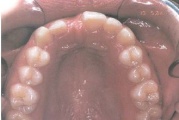

Laste ja noorukite söömishäired. Anorexia nervosa, Bulimia nervosa